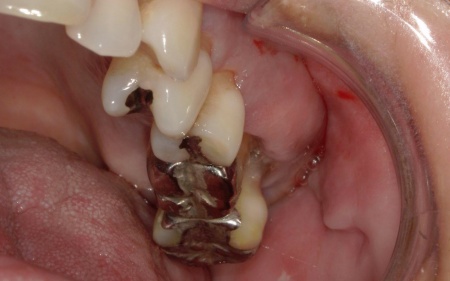

拝見したところ、左上の抜歯部周辺は歯を支える骨が溶ける「骨吸収」が進行し、隣接している歯を含めた複数の歯がひどくグラグラしており、温存が困難です。

噛み合わせも安定していなかったため、このままでは残っている歯への負担が増加し、歯の揺れやさらなる噛み合わせの悪化につながるリスクがあります。

右下奥歯は2本欠損しており、親知らず(第3大臼歯)と手前の奥歯(第2小臼歯)の2本でブリッジを支えていますが、これは親知らずに過度な負荷がかかる構造です。

親知らずはすでに大きく傾いており、こちらも温存が難しいため、ブリッジを除去してから親知らずを抜く必要があります。